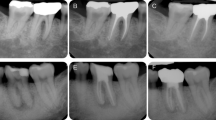

In human extracted teeth, the effect of two decalcifying solutions in removing Ca(OH)2 is illustrated in Figure 4. There were no significant differences in any sections of the canal irrigated either with 10% citric acid or with 17% EDTA in removing Ca(OH)2 (P>0.05). For 33% of the samples, Ca(OH)2 was completely removed by 10% citric acid. Residual Ca(OH)2 was found in the apical one-third, isthmus and irregular parts (Figure 5).

Micro-CT reconstructed images of extracted teeth. (a1–a3) Reconstructed images after root canal preparation, Ca(OH)2 medication and removal with 10% citric acid. (b1–b3) Reconstructed images after root canal preparation, Ca(OH)2 medication and removal with 17% EDTA. EDTA, ethylenediaminetetraacetic acid; micro-CT, micro-computed tomography.